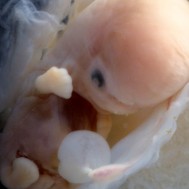

Baby: Week 6

You’re now making spontaneous movements, and can twitch your trunk and limb buds

Each day, changes make you more recognisable as a small person just like you. Now your lungs are forming![1] Brain function, as measured by EEG waves, can be recorded within days.[2] Nerve cells in the brain are connecting, forming primitive neural pathways. Your hands can bend at the wrist, and webbing is disappearing from your feet. Your tail is just about gone. Tastebuds are forming on your tongue.[3] You’re now making spontaneous movements, and can twitch your trunk and limb buds.[4]